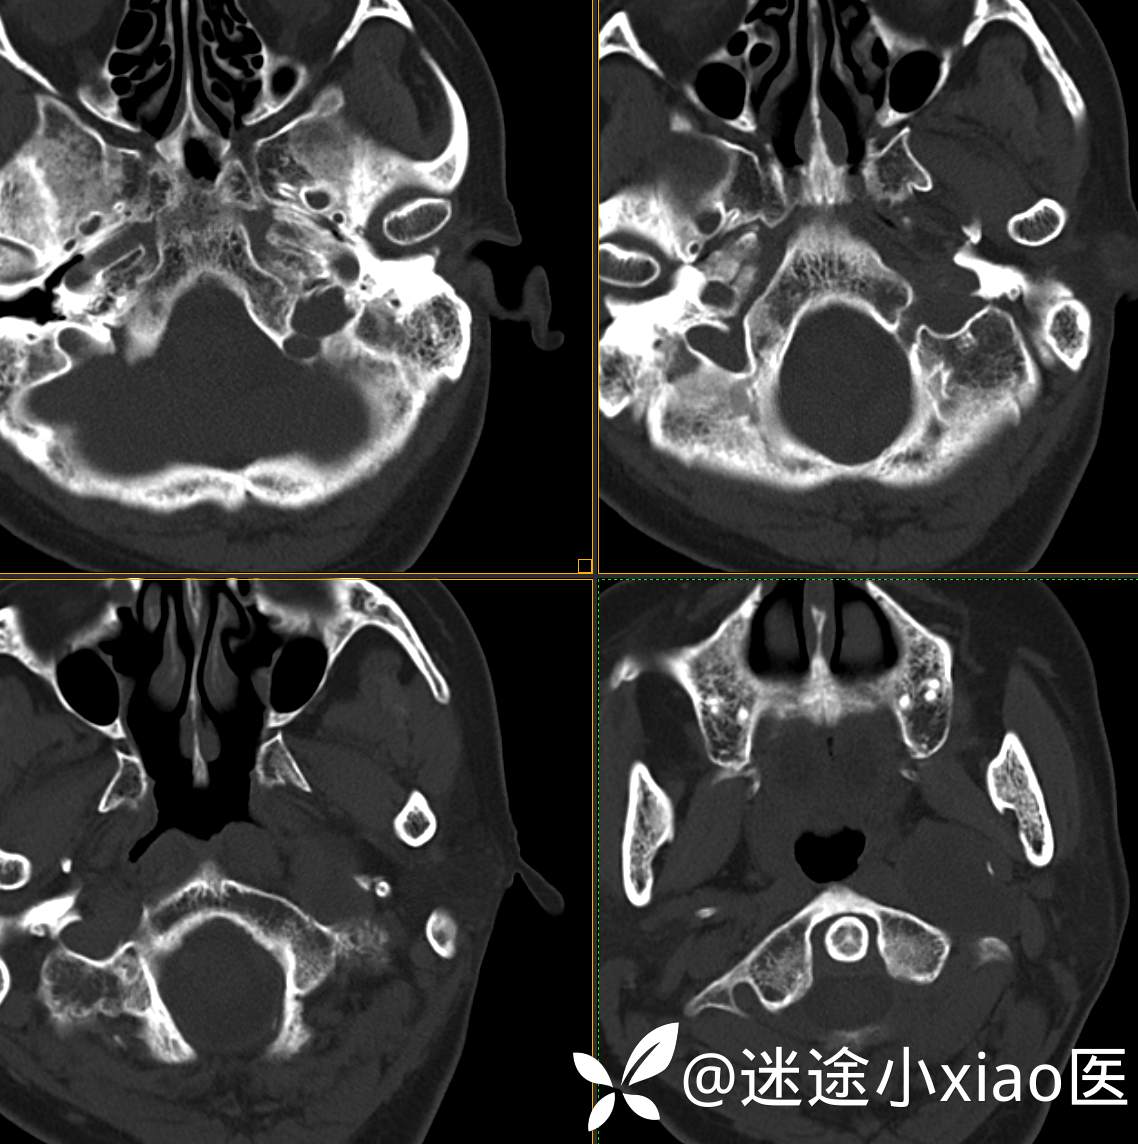

头颈组17:颈静脉孔区占位,副神经节瘤?神经鞘瘤?脑膜瘤?

患者性别:女

患者年龄:57岁

主 诉:  声音嘶哑进食困难伴左侧颌部麻木半年

现病史:  【患者半年前无明显诱因出现声音嘶哑,进食困难,只能进食糊状食物,伴有恶心呕吐,无明显头痛头晕,未加重视。